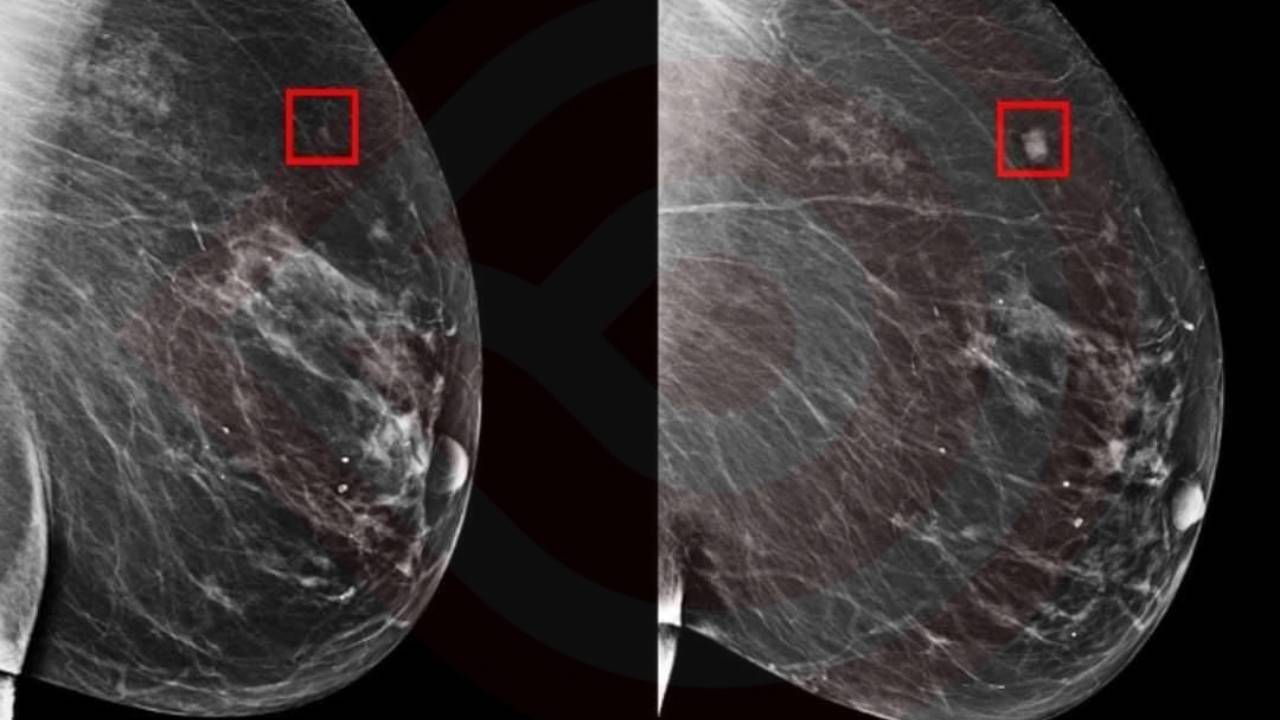

El modelo AsymMirai utiliza la comparación bilateral de los tejidos mamarios izquierdo y derecho, un enfoque que hasta ahora solo se empleaba para detectar la presencia de cáncer, pero no para predecirlo en el futuro. Este método permite identificar diferencias sutiles entre ambos lados y utilizarlas para anticipar el desarrollo del cáncer, con una precisión notable que abarca desde uno hasta cinco años de anticipación.

Además, el hecho de que AsymMirai permita identificar diferencias localizadas en el tejido mamario puede servir como una herramienta adicional para los radiólogos, reduciendo la dependencia excesiva de algoritmos complejos y promoviendo diagnósticos más precisos.